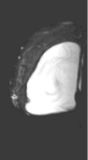

Left images show intracapsular rupture in the left implant ("linguini sign").   Right images from a contrast dynamic scan show an intensely enhancing mass adjacent to a right implant.

High-resolution MRI is extremely accurate for diagnosing silicone and saline implant rupture.   The so-called "linguini sign" refers to serpiginous thin lines seen with intracapsular rupture (left 3 images above).   Various new "silicone techniques" can also detect extracapsular extravasation of silicone.